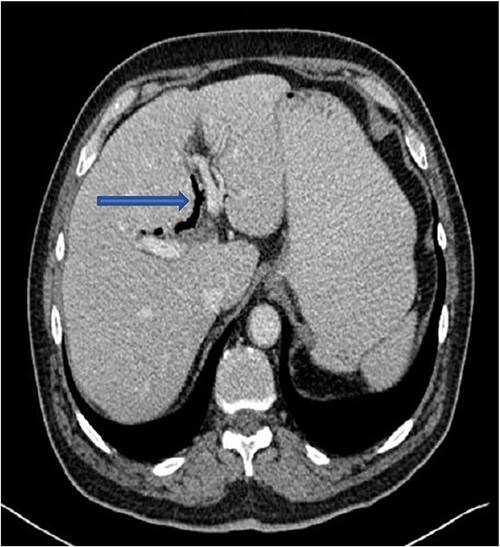

The plain film of the abdomen showed multiple air-fluid levels on the erect film (Fig. 1) and small bowel dilatation on the supine (Fig. 2). The CT showed multiple air pockets in the biliary tree, representing pneumobilia (Fig. 3). It also showed evidence of a circular radio-dense stone measuring 2 cm within the distal jejunum, leading to obstruction and dilatation of the proximal jejunum (Fig. 4).

CT is the investigation of choice. Plain films can reveal dilated small bowels, confirming small bowel obstruction [8]. The presence of Rigler’s triad on the plain film, which includes pneumobilia, dilated bowel, and ectopic gallstones, is diagnostic of gallstone ileus, but this occurs only in 9%–14% of patients [7]. Most patients require surgical intervention to relieve the obstruction. Surgery includes enterotomy and removal of the stone (enterolithotomy) or enterolithotomy with cholecystectomy and repair of the fistula [2]. Commonly, simple enterolithotomy is favored as it carries less morbidity, with or without cholecystectomy at a later date [9]. Spontaneous fistula closure occurs in up to 50% of cases [7].